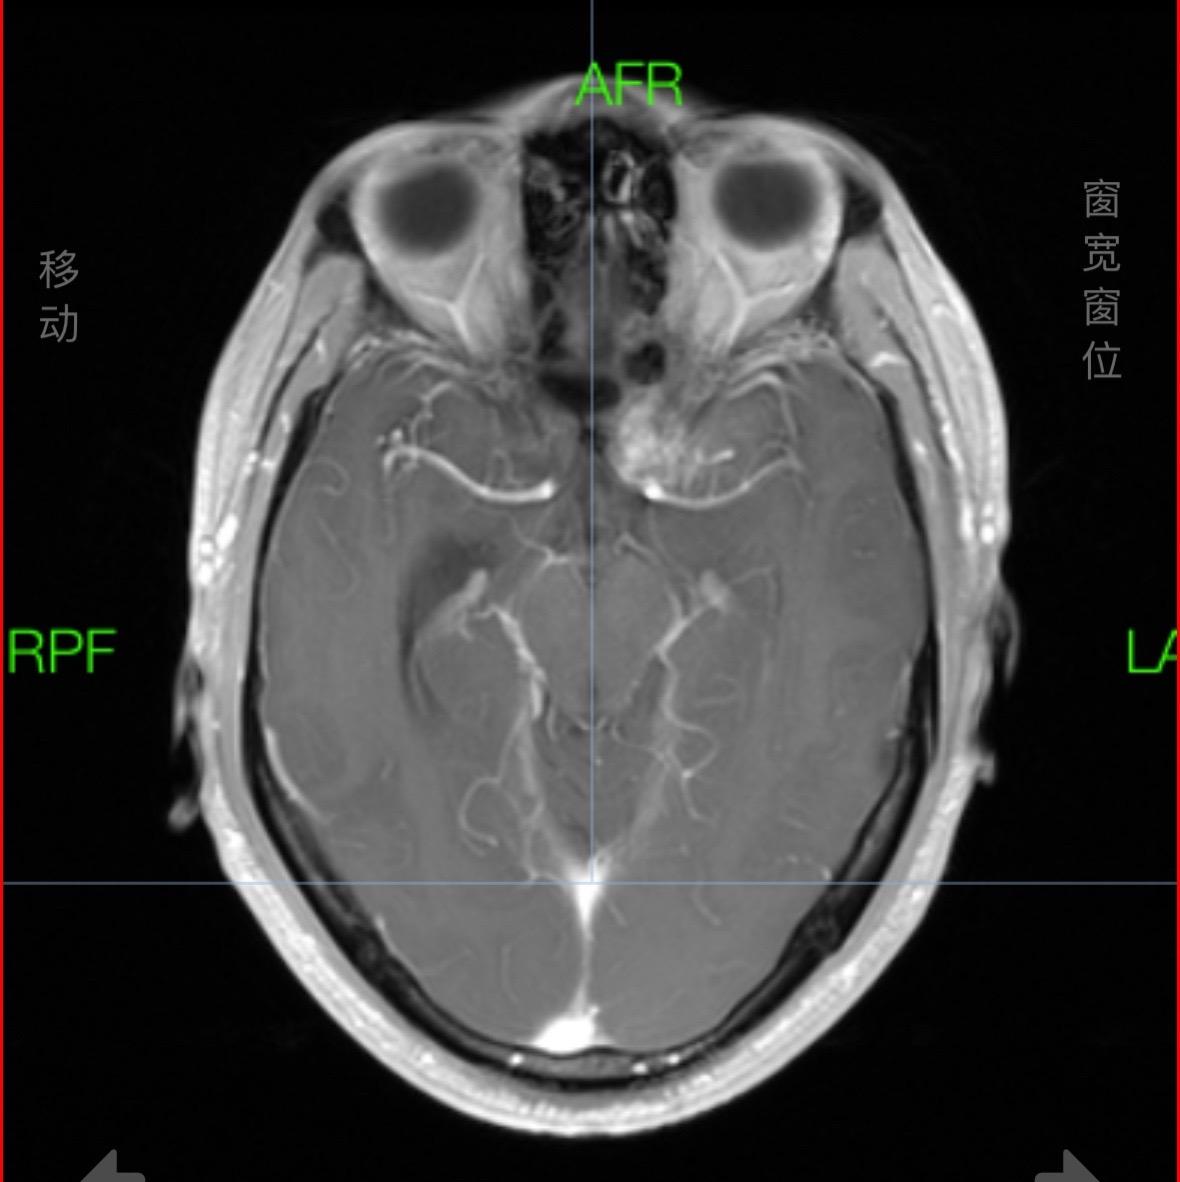

掩盖牙痛的手术。这个肿瘤,周边的重要结构实在太多了,连前交通复合体、内囊前肢、下丘脑、脑室壁、尾状核、中动脉等都一一暴露,如刀尖上行走,手术中导航加持,术中磁共振如同老师一般给你阅卷打分,没想到术中的专注还有意想不到的效果,因为做手术前牙痛,没想到都因为专注做完手术还好了点,看来没入错行,一举两得!